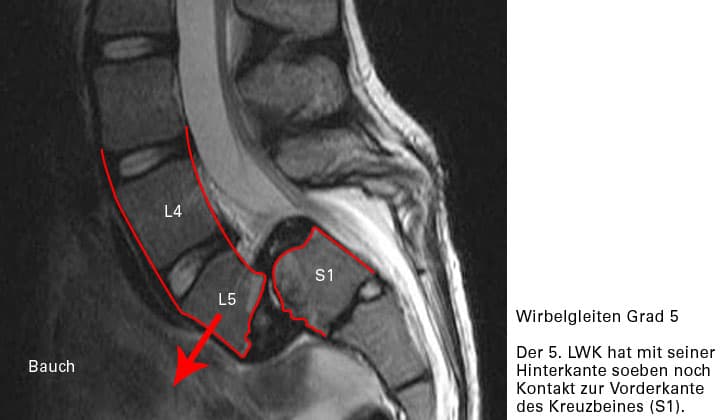

Grad V

Der Gleitwirbel kippt vom darunter liegenden Wirbel in den Bauchraum ab (extrem selten)